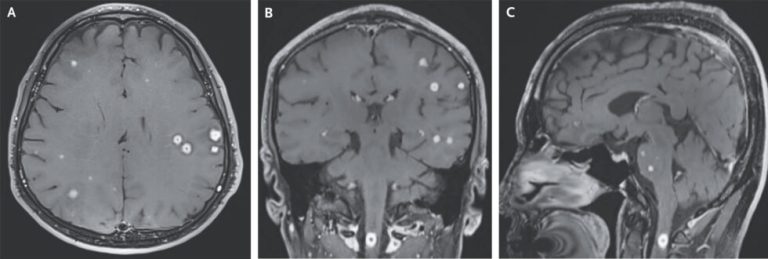

When doctors describe your brain scan as a “starry sky,” it’s not good

A starry sky can be stunning—even inside a hospital emergency room. But instead of celestial bodies…